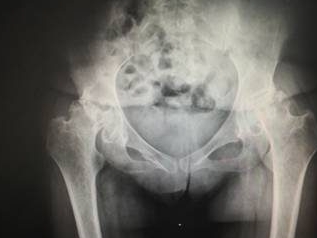

在骨科疾病中,股骨头坏死因早期症状隐匿、易与其他疾病混淆,被不…… 【详情】

股骨头坏死是一种进展性骨组织病变,核心是股骨头血供受损导…… 【详情】

股骨头坏死作为一种慢性骨关节疾病,早期症状隐匿,不少人因认知偏…… 【详情】

在骨科常见的慢性疾病中,股骨头坏死的诱因复杂多样,而长期饮酒是…… 【详情】